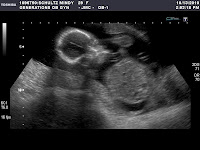

It's a Boy!!

He was moving around a lot and wouldn't get off my bladder. He is already stubborn!